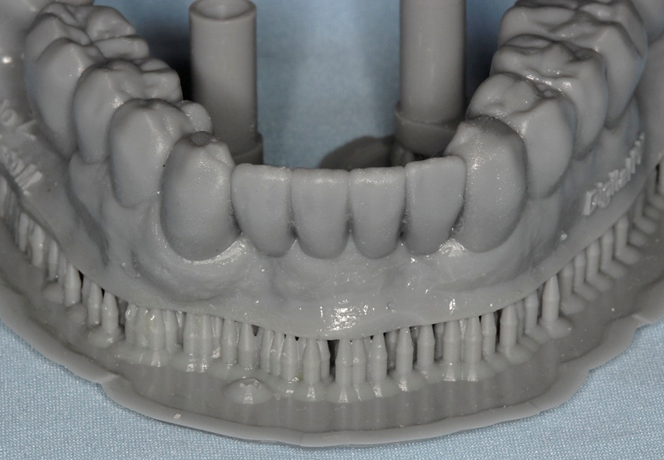

Avaliamos o espaço mésio-distal entre os dentes 33 e 43 e constatamos a ausência de distância para a colocação de implantes individualizados. Assim sendo, optamos pela instalação de dois implantes Veloce CM de diâmetro 3.3 e pilares do tipo micro-cônico para a solução clínica.

Dessa forma, na matéria desta semana, será abordada uma situação clínica de espaço mésio-distal restrito com o uso de implantes híbridos do tipo Veloce CM estreitos de 3.3 de diâmetro e posterior confecção de prótese sobre implantes com pilares intermediários do tipo micro-cônico.

Diante do caso clínico apresentado, constatamos a importância de um correto planejamento, que evidenciou a necessidade de implantes estreitos do tipo Veloce CM e sobre esses implantes os componentes também estreitos do tipo micro-cônico para que os espaços desdentados mésio-distais fossem respeitados de forma adequada.